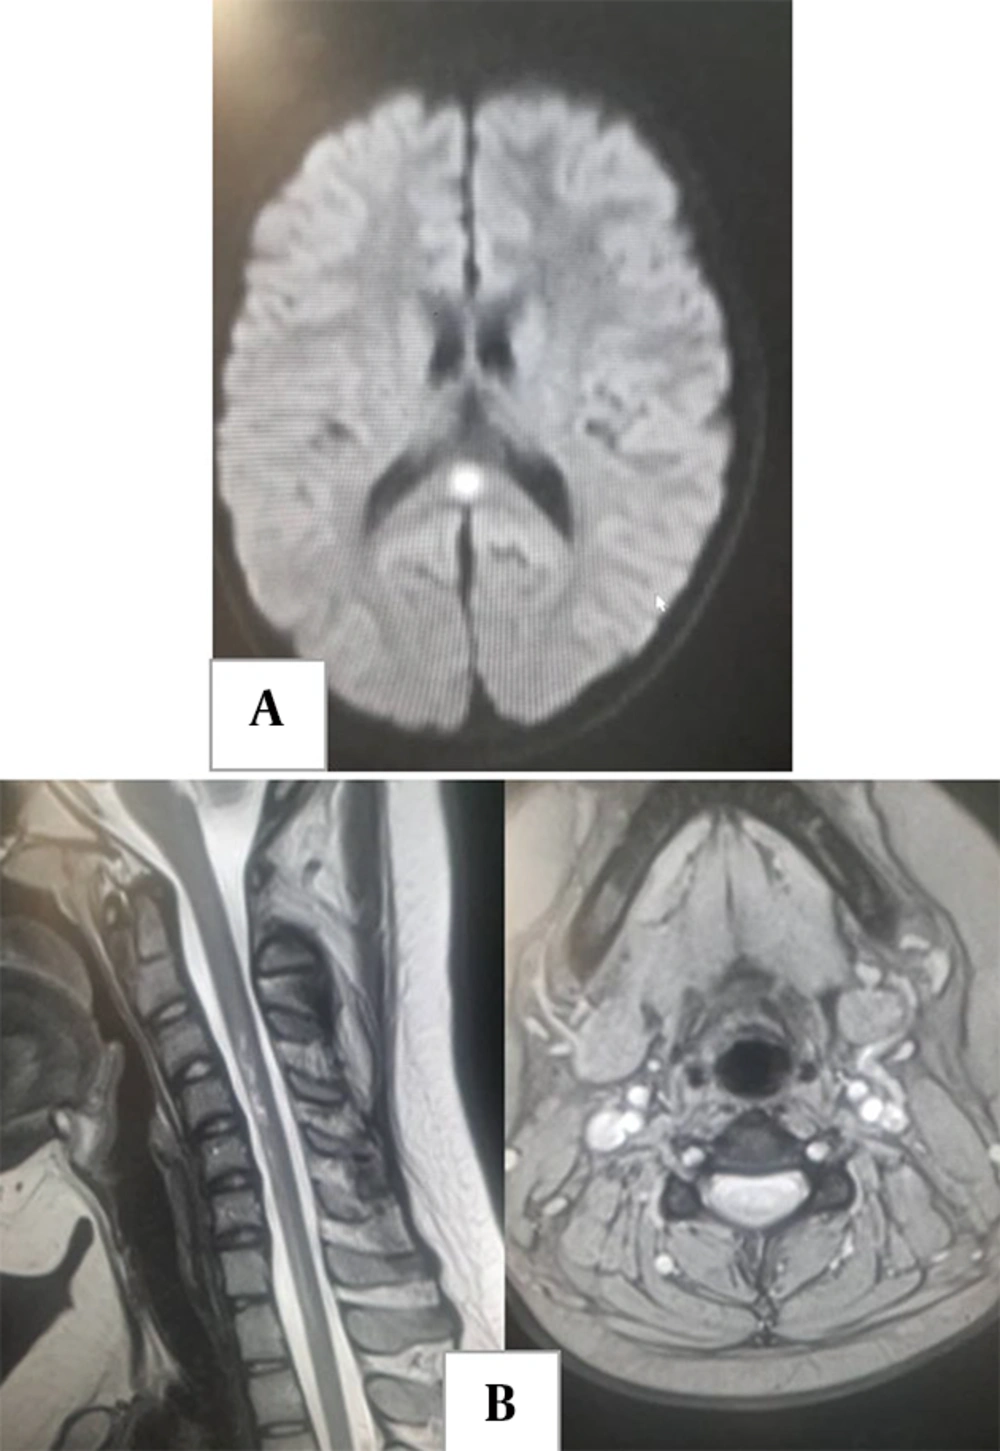

Cerebrovascular complications are less common in children than in adults. Ischemic stroke due to vasculitis is possible in MIS-C but is also a known complication of intravenous immunoglobulin treatment. Common neuroimaging patterns involve immune-mediated para-infectious processes affecting the brain, spine, and nerve roots (Figure 4A and B) (42, 47).

A, brain computed tomography (CT) without contrast and CT angiogram in a 7-year-old boy with a diagnosis of multisystem inflammatory syndrome in children (MIS-C) who presented with left hemiparesis. Images show hypodensity in the territory of the right middle cerebral artery (ischemic infarct). The CT angiogram shows duplicated middle cerebral artery on the right side as a variant. B, brain CT in a 12-year-old boy with a diagnosis of MIS-C who presented with headache and seizure during treatment, demonstrating asymmetric bilateral subcortical hypodensity in parieto-occipital lobes compatible with posterior reversible encephalopathy syndrome. C, acute disseminated encephalomyelitis (ADEM) in an 8-year-old girl with recent history of coronavirus disease 2019 (COVID-19) who presents with loss of consciousness. Fluid-attenuated inversion recovery images show scattered abnormal signal in subcortical white matter and bilateral thalami.

Typical brain manifestations include acute disseminated encephalomyelitis (ADEM)-like appearances (Figures 4C and 5A), characterized by T2 hyperintense lesions in grey and white matter, sometimes with restricted diffusion or enhancement and occasionally resembling Guillain-Barre syndrome (42, 53, 54). Myelitis and neuritis are other potential presentations (Figure 5A and B) (55).